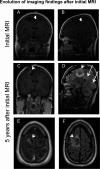

We present two natalizumab-treated multiple sclerosis patients who developed glioblastoma multiforme (GBM) with variable outcomes. One patient had an isocitrate dehydrogenase (IDH)-wildtype GBM with aggressive behavior, who declined treatment and died 13 weeks after symptoms onset. The other patient underwent resection of an IDH-mutant secondary GBM that arose from a previously diagnosed grade II astrocytoma. He is still alive 5 years after the diagnosis of GBM. JC virus was not detected in either case. Whether natalizumab played a role in the development of GBM in those patients deserves further investigation.